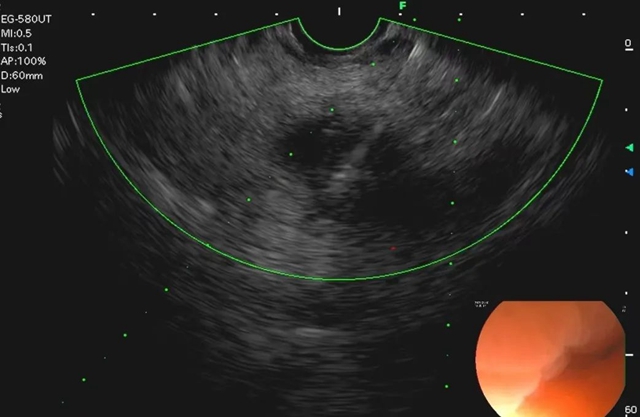

经过超声内镜全面扫查,最终在税先生的胰腺头颈部发现了一个2.2×2.3cm大小的低回声病灶,超声下显示比之前CT检查时更大。

在多普勒超声引导下,谨慎避开周围血管,选择合适的穿刺位置后,李丽副教授用穿刺针对病灶进行了反复多次抽吸。穿刺过程十分顺利,成功获取了有效的病灶组织。